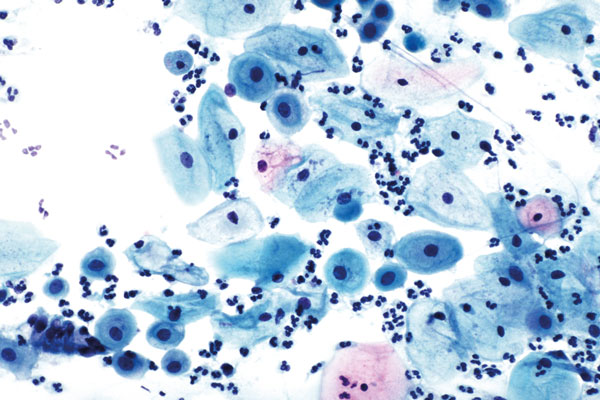

richtige Antwort:

b. Mykose und Leptothrix

- fadenförmige Bakterien

- keine Septierung erkennbar, nicht zu verwechseln mit den Hyphen bei Mykose

- neben den Bakterien liegen an den Zellen die Sproßzellen der Mykose